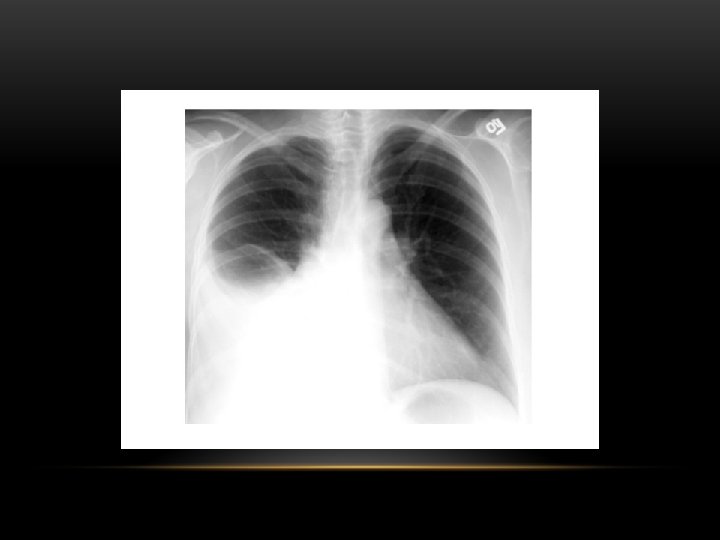

Pneumothorax • No vascular markings on right • No shift of mediastinum to left • Atelectasis right lung • Increased haziness on left: Diversion of entire cardiac output • Small fluid level near costophrenic angle: Hydro pneumothorax